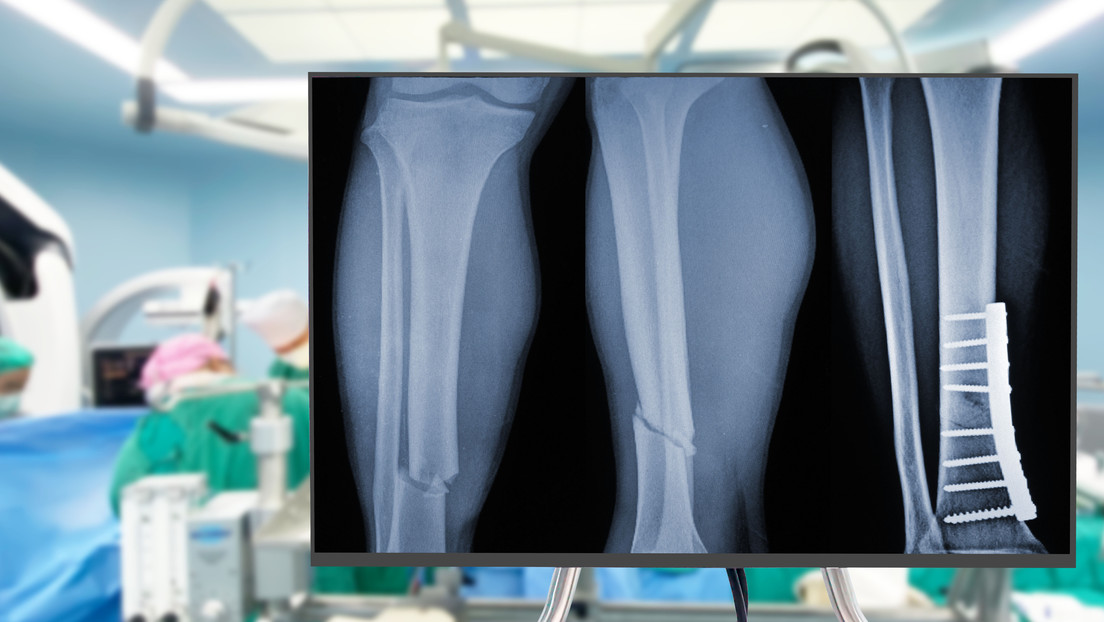

Imagen ilustrativa. 123RF

- Su tecnología es capaz de unir y fijar con precisión fragmentos óseos en minutos y con una incisión mínimamente invasiva. Gracias a su tecnología adhesiva, el pegamento, bautizado como Bone 02, ha logrado unir y fijar en unos pocos minutos distintos fragmentos óseos mediante una incisión de 2 a 3 centímetros que resulta mínimamente invasiva.

Gracias a su tecnología adhesiva, el pegamento, bautizado como Bone 02, ha logrado unir y fijar en unos pocos minutos distintos fragmentos óseos mediante una incisión de 2 a 3 centímetros que resulta mínimamente invasiva.

Un seguimiento de tres meses a más de 150 casos de aplicación del material ha demostrado que este favorece un proceso de cicatrización sin complicaciones, con la recuperación total de las funciones de las partes óseas tratadas.

El material, inspirado en las ostras, representa un avance significativo respecto de los procedimientos tradicionales, que utilizan placas de metal para recuperar los huesos atendidos.